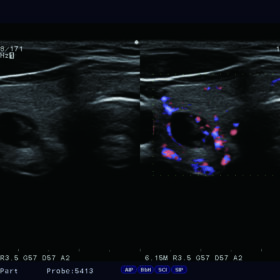

Ultrasound Aloka Prosound F37 – Image Gallery and Videos

Dual Dynamic Display (DDD)

A B-mode image and Flow mode image can be displayed side-by-side in real time. In Hitachi Aloka F37 the DDD assists easy anatomical understanding of blood flow. The function can be used with both power flow and eFLOW.